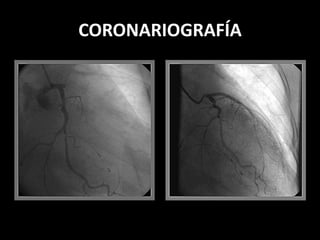

CORONARIOGRAFÍA

VASCULARIZACIÓN DEL CORAZÓN

A- ARTERIA CORONARIA DERECHA

- r. ventriculares y auriculares

- art. Marginal derecha

- r. septales para N. de A. Tawa

“ Haz de His

B- ART. CORONARIA IZQUIERDA

- Da 2 ramas:

ART. DESCENDENTE ANT.

-r. ventriculares y septales

- art. Adiposa de Vieussens

- parte del sist. de

conducción

ART. CIRCUNFLEJA

- art. Marginal izquierda

- termina en la Cruz de HAS